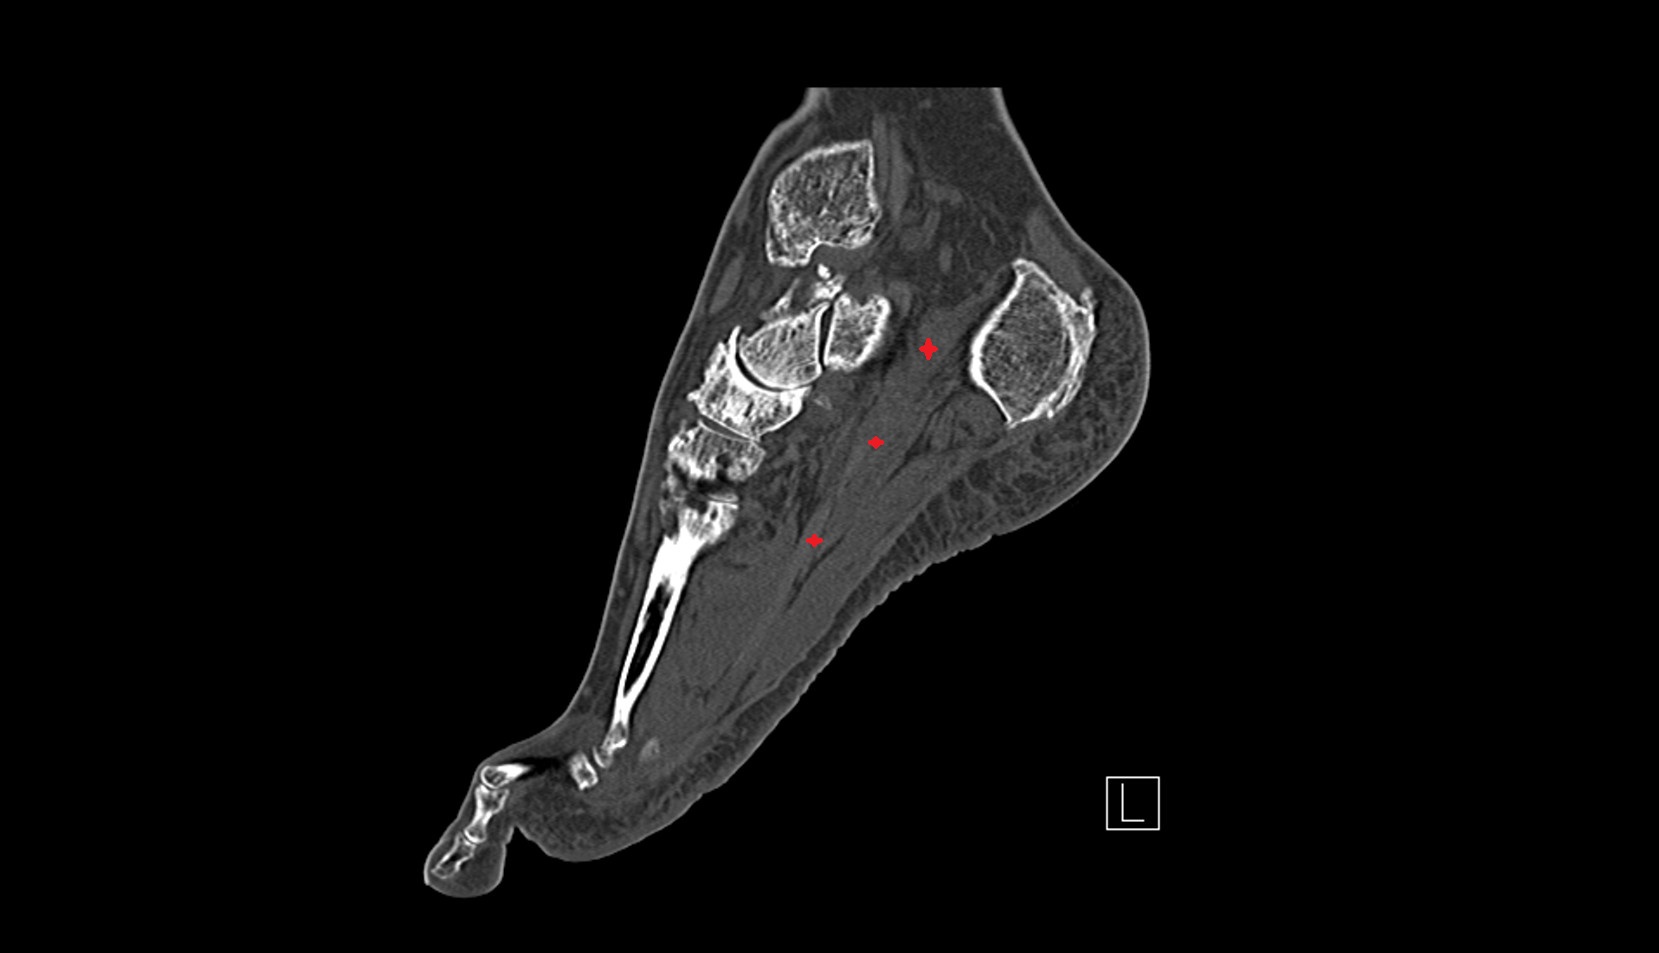

- Talus

- Head of talus

- Body of talus

- Neck of talus

- Calcaneus

- Anterior process of calcaneus

- Sustentaculum tali

- Cuboid

- Ankle joint

- Talocalcaneal joint

- Talocalcaneonavicular joint

- Calcaneocuboid joint